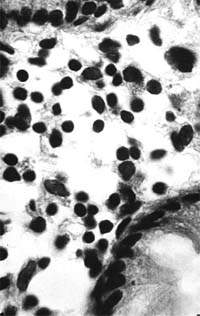

| Рисунок 1. Слизистая оболочка толстой кишки при ротавирусном гастроэнтерите. Минимально выраженный катаральный колит. х 100. |

В клинической практике врач нередко сталкивается с обстоятельствами (сомнительные результаты вирусологических и серологических исследований, случаи микст-инфекций), когда возникает необходимость в применении дополнительных методов для верификации диагноза. С этой целью может быть использован доступный для практического здравоохранения интрументальный метод исследования — ректороманоскопия с аспирационной биопсией слизистой оболочки толстой кишки. При гистологическом, морфометрическом и гистохимическом исследованиях биоптатов при ротавирусном гастроэнтерите выявляются характерные изменения в виде поверхностного минимально выраженного катарального колита с незначительной дистрофией эпителия (рис. 1), снижения числа серотонинсодержащих желудочно-кишечных эндокриноцитов (ЕС-клетки) в эпителиальном пласте кишечных желез, умеренной инфильтрацией собственной пластинки плазматическими клетками и увеличением в ней числа макрофагов (рис. 2). Эти особенности имеют дифференциально-диагностическое значение, поскольку отличаются указанным показателем от других острых кишечных инфекций, что может быть использовано в диагностически сложных случаях.